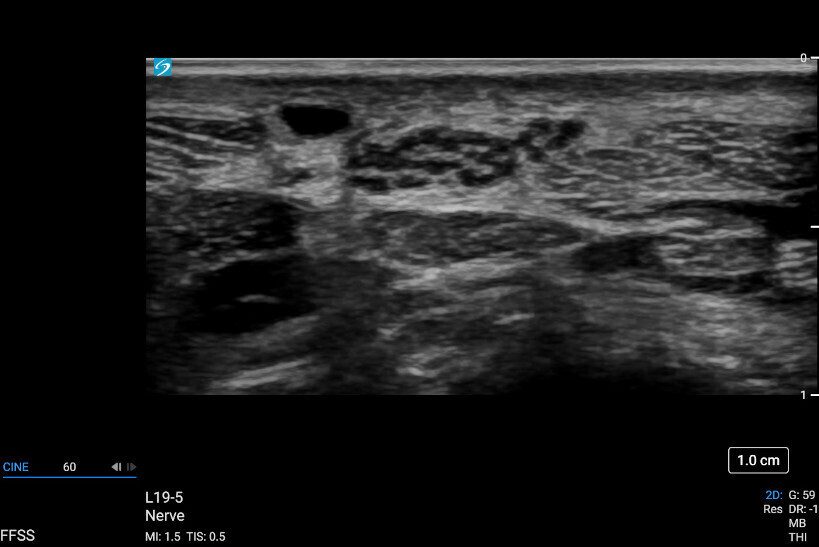

Sonosite PX, hastaları tedavi ederken ve teşhis ederken güven için en gelişmiş görüntü netliğimizi bünyesinde barındırır. Arayüz, geliştirilmiş verimlilik için dokunmatik ve fiziksel kontrolleri bir araya getirirken, uyarlanabilir yataydan dikeye çalışma yüzeyi optimum yatak başı ergonomisi sağlar. Sonografik dönüm noktalarını daha doğru bir şekilde görselleştirmek için Sonosite’in en gelişmiş görüntü netliği ve optimum hasta bakımı için ses kontrolü.

Üstün Görüntü Kalitesi

Daha iyi görüş, daha derin anlayış. Sonosite, klinisyenlerin en zorlu ihtiyaçlarını karşılamak için yeni bir görüntü performansı standardını yeniden tanımlıyor.